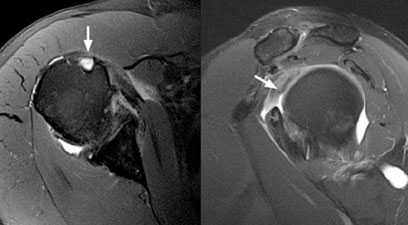

Пример массивного ретрагированного разрыва вращательной манжеты с гетеротопической оссификацией разорванных сухожилий